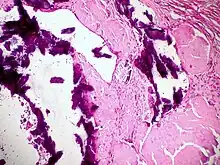

Diagnosis of amyloidosis generally requires tissue biopsy. The biopsy is assessed for evidence of characteristic amyloid deposits. The tissue is treated with various stains. The most useful stain in the diagnosis of amyloid is Congo red, which, combined with polarized light, makes the amyloid proteins appear apple-green on microscopy. Also, thioflavin T stain may be used.[11] A number of imaging techniques such as a DPD scan or SAP scan are also in use.[12]

Tissue can come from any involved organ, but in systemic disease the first-line site of the biopsy is subcutaneous abdominal fat, known as a "fat pad biopsy", due to its ease of acquisition versus biopsy of the rectum, salivary gland or internal organs. An abdominal fat biopsy is not completely sensitive, and sometimes, biopsy of an involved organ (such as the kidney) is required to achieve a diagnosis.[11] For example, in AL amyloidosis only 85% of people will have a positive fatpad biopsy using Congo red stain.[6] By comparison, rectal biopsy has sensitivity of 74–94%.[7]